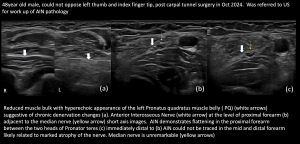

3.Anterior Interosseous Nerve (AIN) Pathology with pronator quadratus (PQ) atrophy

4.Anterior Interosseous Nerve with concurrent Carpal Tunnel Syndrome